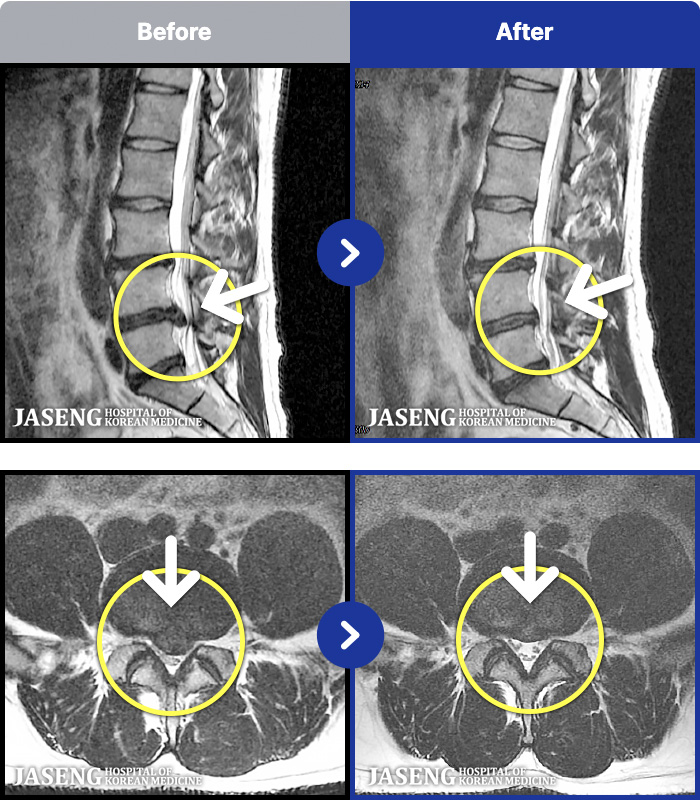

MRI ġ

88 MRI ũ ʸ Ȯϼ.